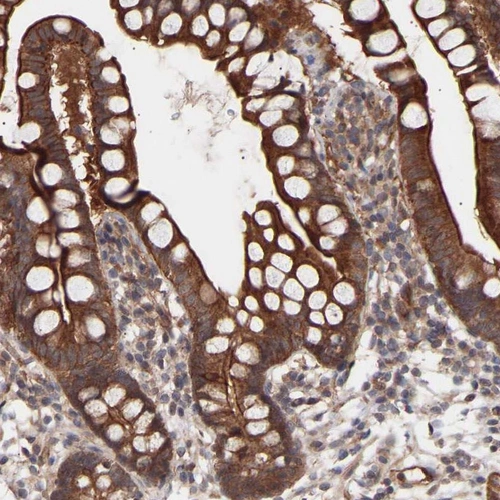

Immunohistochemical staining of human small intestine shows strong cytoplasmic positivity in glandular cells.